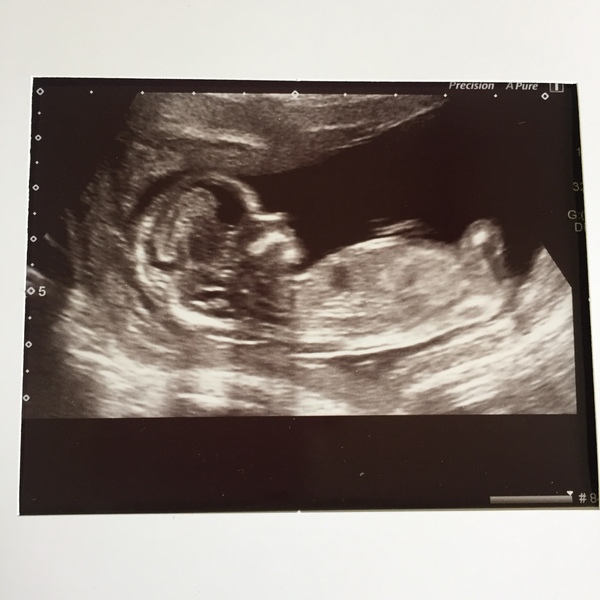

Pleased to report that all is well- so far. I have gained almost a week somehow and now 13.4 weeks edd 21st December. Took ages as Baby was doing head stands-

More cake for more babies... BFP after MC

Awesome pic @Primrose16. Huge congratulations.

@Primrose16 it looks like bub has hands behind his head. I think it's a boy!! 😍😍

@Primrose16 wow what a beautiful photo! Congratulations!!

Thanks all. My little girl (18 months) grabbed the photo from the table, looked and said baby. I’m surprised she saw a baby in the photo as they are not very clear for children.